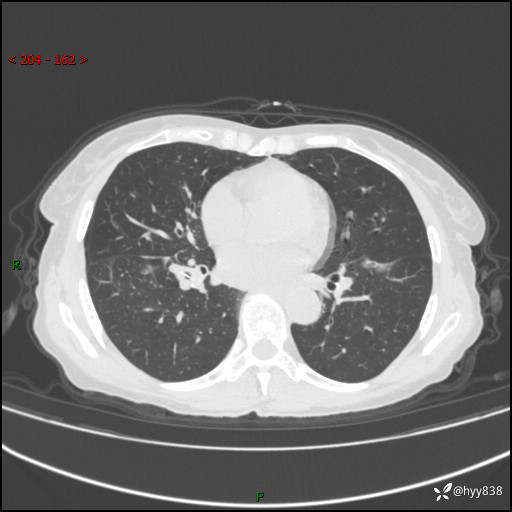

患者性别:男

患者年龄:69岁

简要病史:咳嗽咳痰2月,夜间加重

临床诊断:感染

胸部CT平扫